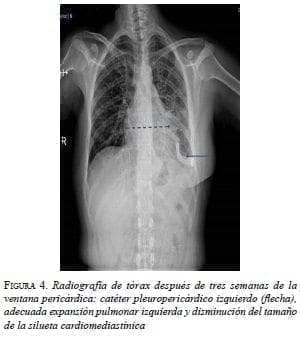

El drenaje pleuro-pericárdico temporal se mantuvo durante tres semanas hasta que los gastos fueron menores de 50 ml. La radiografía de tórax mostró la posición del catéter pleuropericárdico, una adecuada expansión pulmonar izquierda y disminución del tamaño de la silueta cardiomediastínica (figura 4).